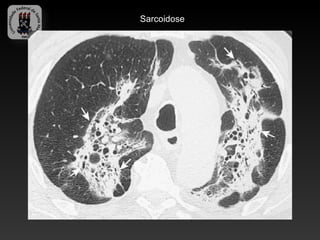

-SARCOIDOSE

-Doença idiopática caracterizada por granulomas não caseosos.

-Envolvimento pulmonar bilateral é o habitual e a linfadenopatia é a manifestação

intratorácica mais comum.

-Cerca de 10% tem radiografia de torax normal.

-Infecção sobreposta é responsável por uma significativa morbidade e mortalidade.

-Achados da TC:

-   Linfadenopatia (75-80%), calcificações em casca de ovo

-   Áreas de atenuação em vidro fosco

-   Nódulos subpleurais e perivascular

-   Espessamento irregular peribroncovascular e dos septos interlobulares

-   Predomínio nas regiões médias e superiores

-   Fibrose – complicação tardia

Sarcoidose